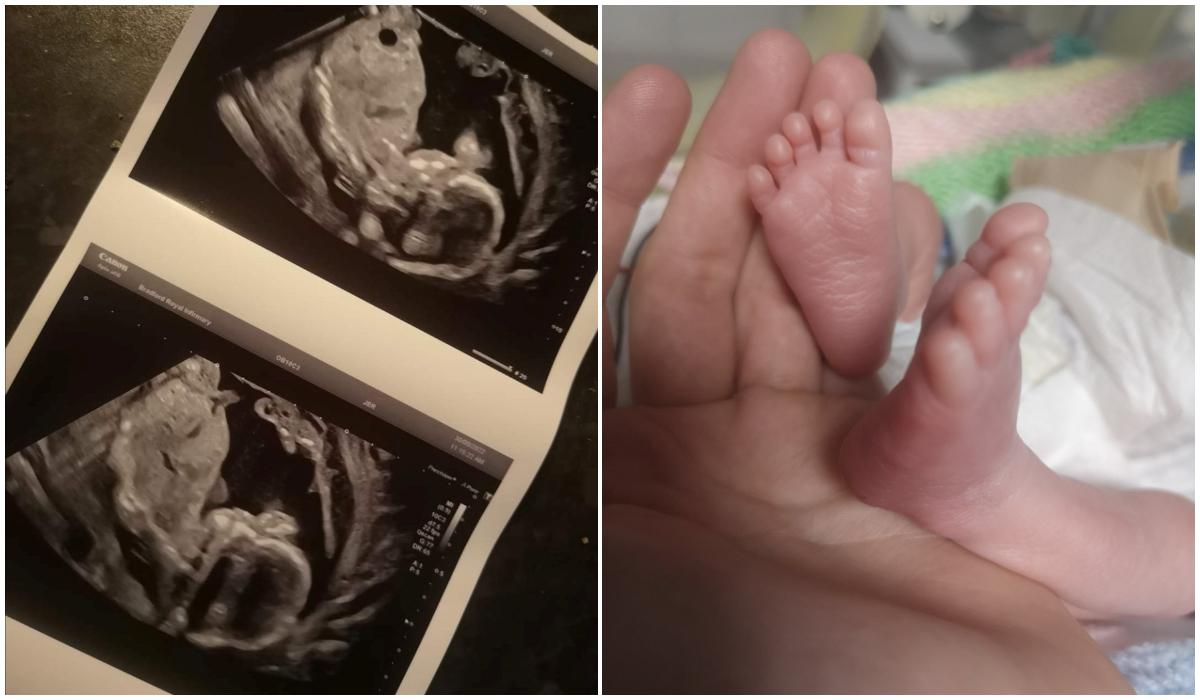

"Miracolul meu de Crăciun". O femeie din UK a devenit mamă deși medicii i-au spus că bebelușul a murit în pântece

O femeie din UK a devenit mamă deși medicii i-au spus că bebelușul a murit în pântece | Sursa foto: Profimedia